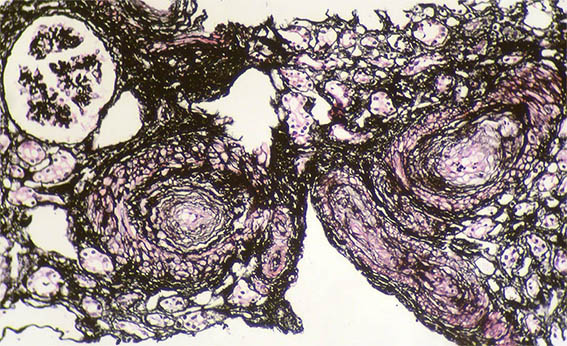

Se hace biopsia renal con impresión diagnóstica de lesión renal aguda. Ver las imágenes.

Figura 1. Trcrómico de Masson, X100.

Figura 2. Tricrómico de Masson, X200.